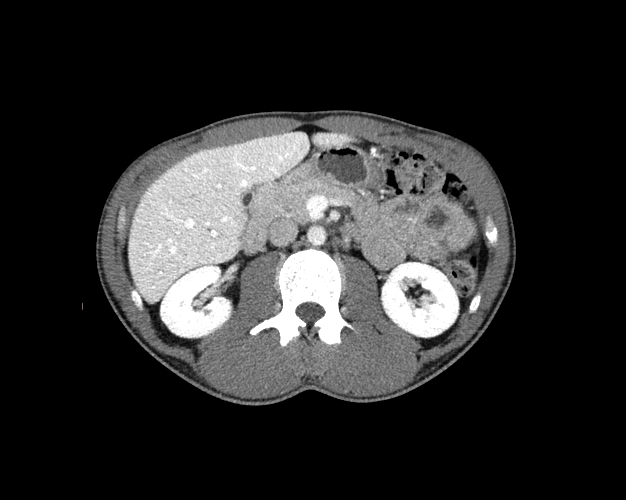

Body

Covers abdominal CT anatomy.